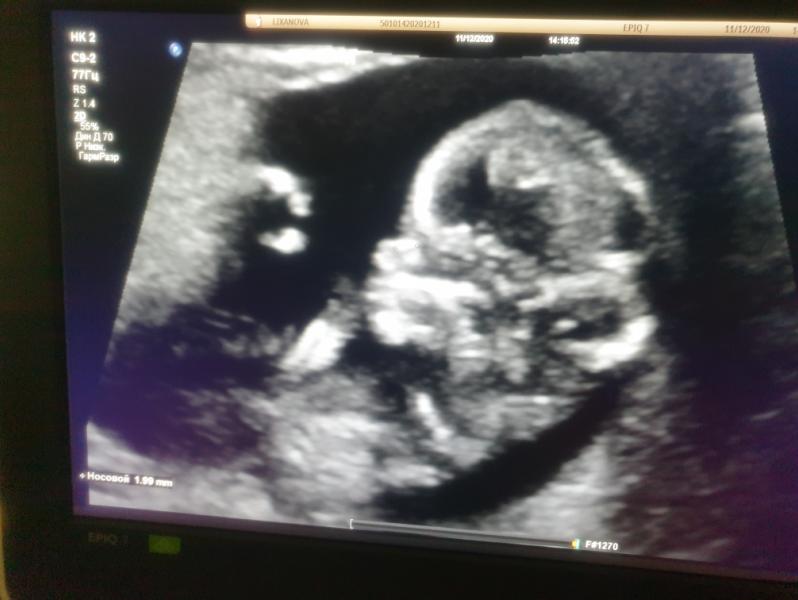

Наше первое УЗИ на 12,6 недель, мой сладулик #немогуналюбоваться